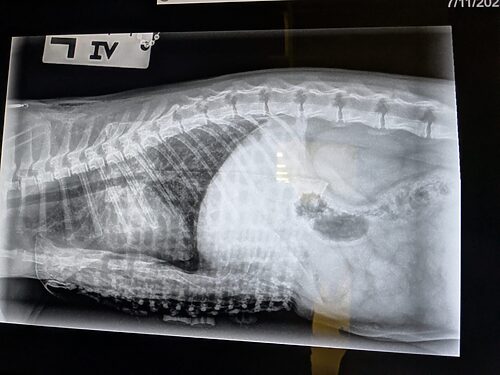

When the day of the operation arrived, Dr. Young was nervous but determined. Vanilla Bean’s case was severe, one of the worst her professor had ever seen. The surgery presented risks, but the prospect of giving Vanilla Bean a significantly improved quality of life was all the motivation Dr. Young needed. The two veterinarians got to work, painstakingly threading each suture under the sternum, careful not to damage any internal structures, especially the heart. After completing all twelve sutures and anchoring them to an external splint, the surgery was complete.

Over the next several weeks, Vanilla Bean returned to our clinic to see Dr. Young and have his bandages changed before returning to the comfort of his foster home. Four weeks later, he was finally able to have the splint removed for good, with the skin beneath the cast healing well. Even more exciting, Vanilla Bean found a new home!